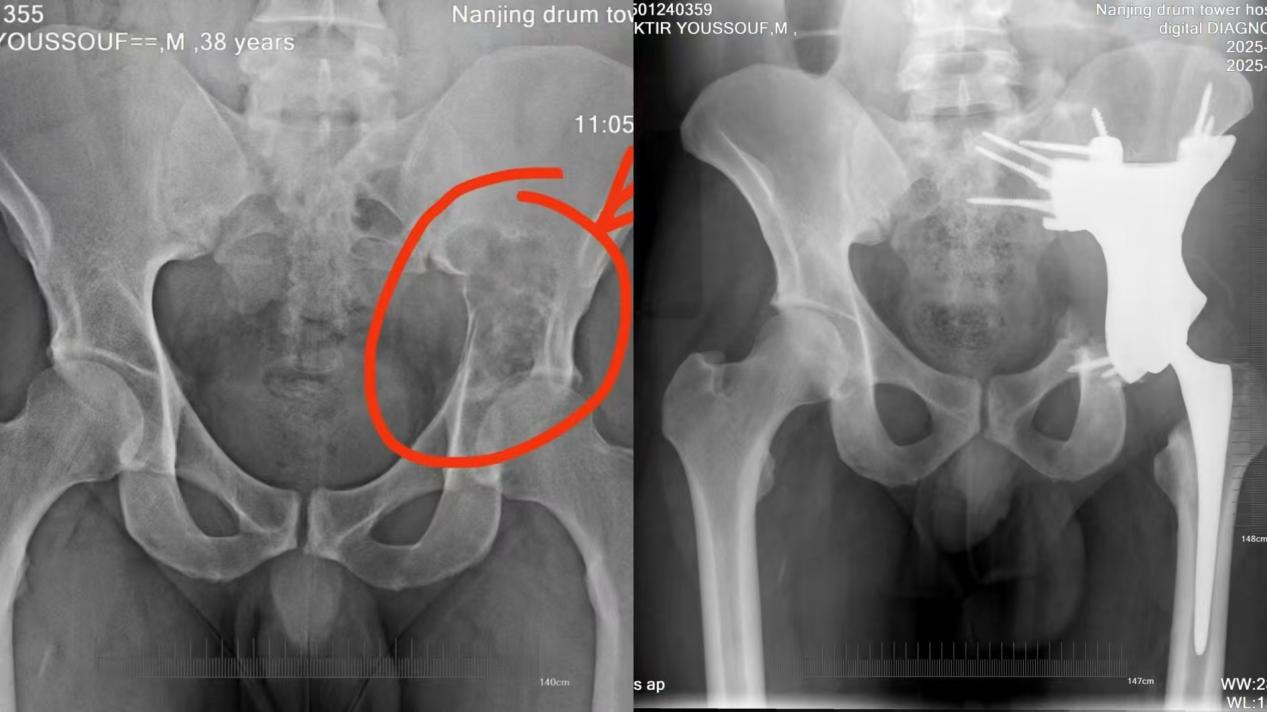

患者BOUKTIR YOUSSOUF来自非洲的阿尔及利亚,今年39岁,在阿尔及利亚体检时发现左侧髋部病变3年,近1年来出现疼痛伴活动受限。BOUKTIR YOUSSOUF的髋部病变不是简单的关节炎,预估是长了肿瘤,切除后还需要骨盆重建。阿尔及利亚当地医疗条件有限,无法完成如此复杂的骨盆切除重建手术。

2024年12月19日,BOUKTIR YOUSSOUF在南京鼓楼医院王守丰主任医师门诊完善磁共振(MR)检查,疑为软骨瘤肉瘤。2024年12 月23日,行经皮穿刺骨活检,病理结果显示为软骨源性肿瘤(软骨肉瘤)。由于患者病灶局限,王守丰主任医师团队建议进行完整切除后进一步评估。

“这种骨盆的肿瘤在整个骨肿瘤领域都是非常有挑战性的,因为骨盆的解剖结构比较复杂,髋部病损部位离大血管和内脏都比较近,常规手术并发症会比较多。”王守丰主任告诉记者,随着科技制造的发展,3D打印假体已经成为常规手术的有效补充。“我们会预先制作一个截骨导板,预切除后再植入定制的3D打印假体,两相配合可以达到肿瘤精准切除以及假体精准匹配的效果,最大程度地保留更多正常的骨骼和关节结构,最大限度地恢复行走和运动功能。”

“从住院安排到各种检查再到手术排班,患者的治疗过程整体比较顺利。”南京鼓楼医院骨科副主任医师徐磊磊告诉记者,手术节点临近春节,用血较为紧张“骨盆病损切除术+骨盆重建术”术中缺血一般会达到2000-3000毫升,“我们进行了长达10天的准备,通过义务献血等一点点‘囤’够了手术备血,顺利完成了手术。”徐磊磊告诉记者,随着恢复进程,BOUKTIR YOUSSOUF术后疼痛逐渐缓解,切口愈合良好,术后病理结果确认为“软骨肉瘤,部分区域为去分化为高级别梭形细胞肉瘤”。